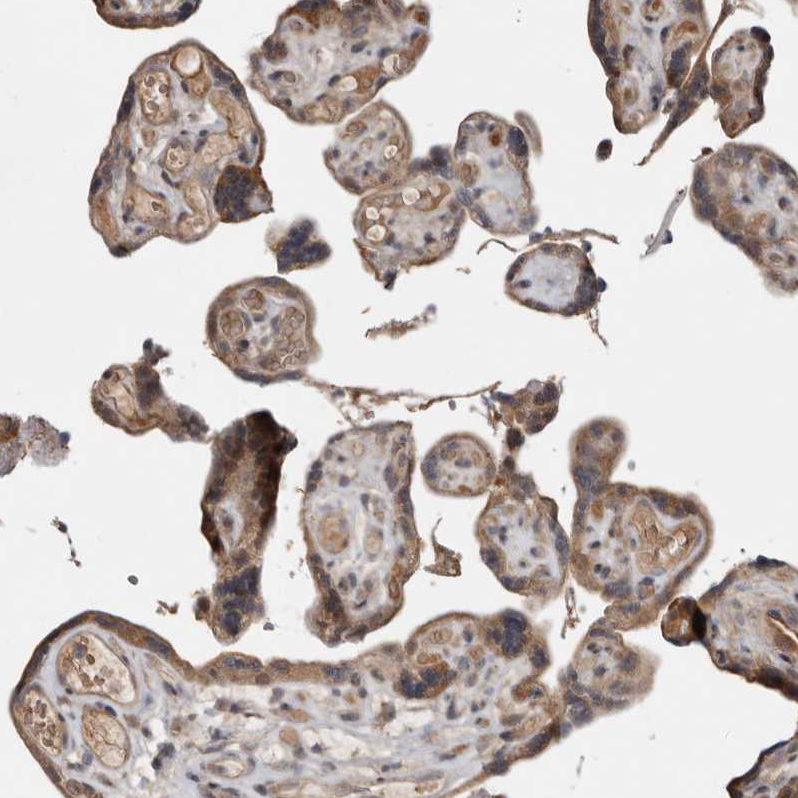

Immunohistochemical staining of human Placenta shows moderate cytoplasmic positivity in trophoblastic cells.